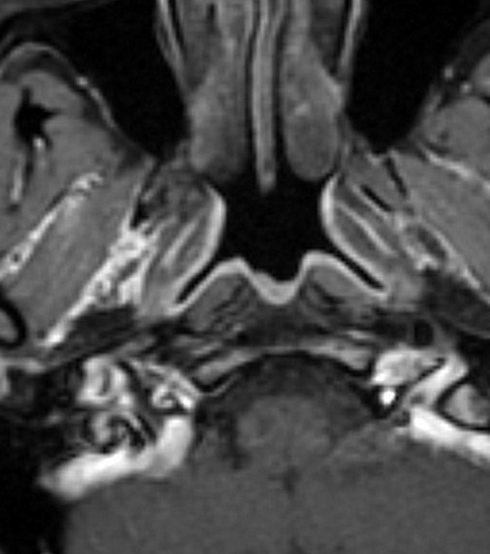

Fossa of Rosenmuller

• Aka posterior-lateral pharyngeal recess

• Most common site for nasopharyngeal carcinoma